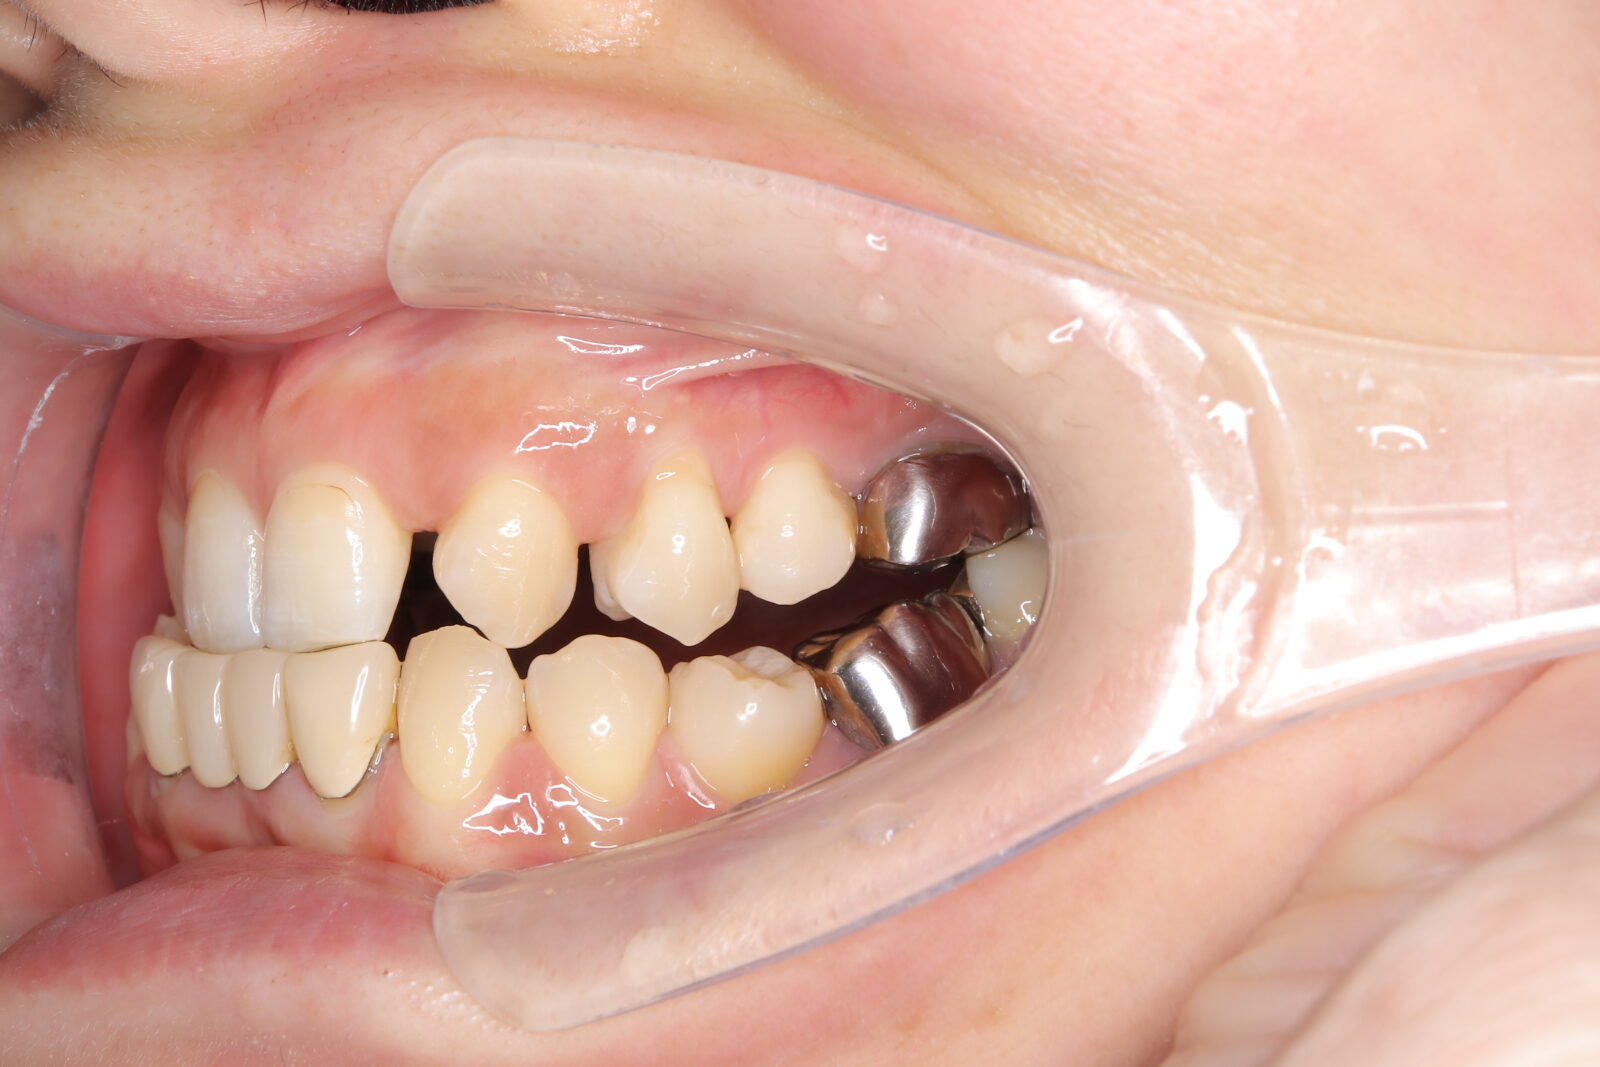

インビザライン(全体矯正)+ホワイトニングコース+セラミック治療の症例

過去にワイヤー矯正で治せなかったクロスバイト。インビザライン(全体矯正)とホワイトニングとセラミック治療で綺麗な笑顔へ。

・費用:726,000円(税込) ※ホームホワイトニングと右上6番ジルコニアクラウン含む

・治療期間:15ヶ月

・通院回数:10回

・32歳女性

-リスクと副作用-

・長時間マウスピースを装着するため、むし歯や歯周病のリスクがある。治療後はリテーナーを装着しないと後戻りしてしまうリスクがある。

・ホワイトニング剤の影響で知覚過敏が起こる可能性がある。色が徐々に戻る可能性がる。

・セラミック:過度な衝撃によって割れることがある。